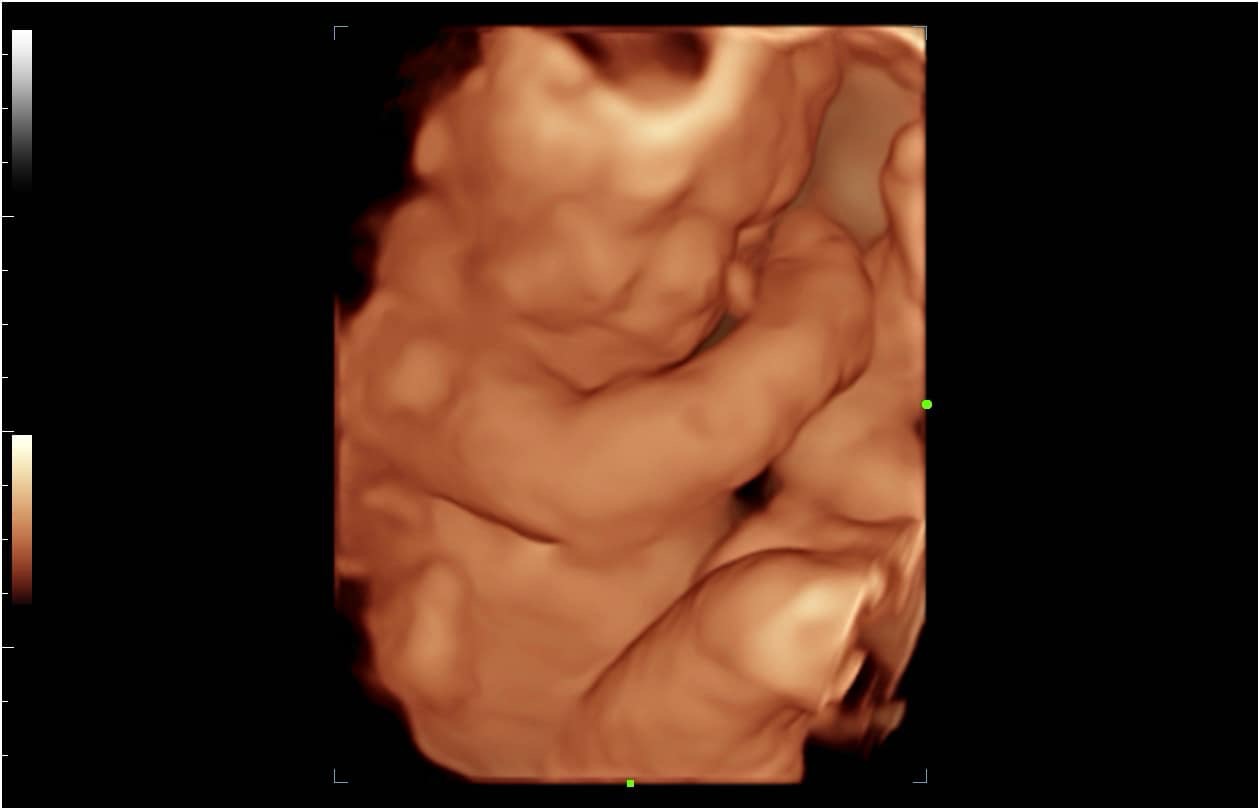

The birth of a new baby is an exciting time for parents, family and friends! At Bonding Moments, we offer a warm family atmosphere that offers Elective 2D/3D/4D and HD prenatal ultrasounds. We use state of the art ultrasound technology that allows our trained technicians to bring your baby to life before your very eyes on an 86 in flat screen TV surrounded by up to 12 of your guests. The realistic images will provide a bonding experience between mommy, daddy, family and friends. See baby yawn, hiccup, smile and kick all in real-time. So, let’s take a journey together and peek inside your baby’s world!

A prenatal ultrasound uses a transducer to deliver high frequency sound waves. Echoes of the sound waves are recorded and transformed into pictures. A gel is applied to the belly and transducer before the scan which helps conduct the sound waves. 2D and 3D are still images .4D adds motion and dimension so it looks like a video and HD adds more realism.